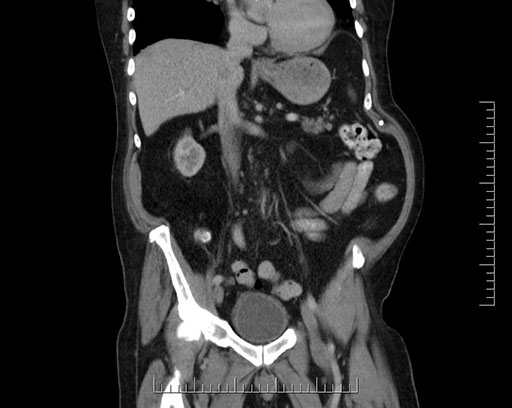

Imaging Analysis

Look through the patient's CT scan to identify any areas of concern for the necessary procedure.

Based on your CT findings, which issue(s) would give reason for "planned slowing down moment(s)" in this case?

Considering a standard Whipple procedure, what step(s) of the operation would you do differently in this case?